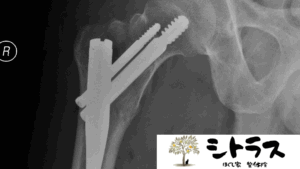

7. 病院に行くべき症状のサイン

次のような症状がある場合は、ただのぎっくり腰ではなく別の疾患の可能性があるため医療機関の受診が必要です。

- 足のしびれや力が入らない

- 排尿・排便障害がある

- 発熱を伴う腰痛

- 安静にしても改善しない強い痛み